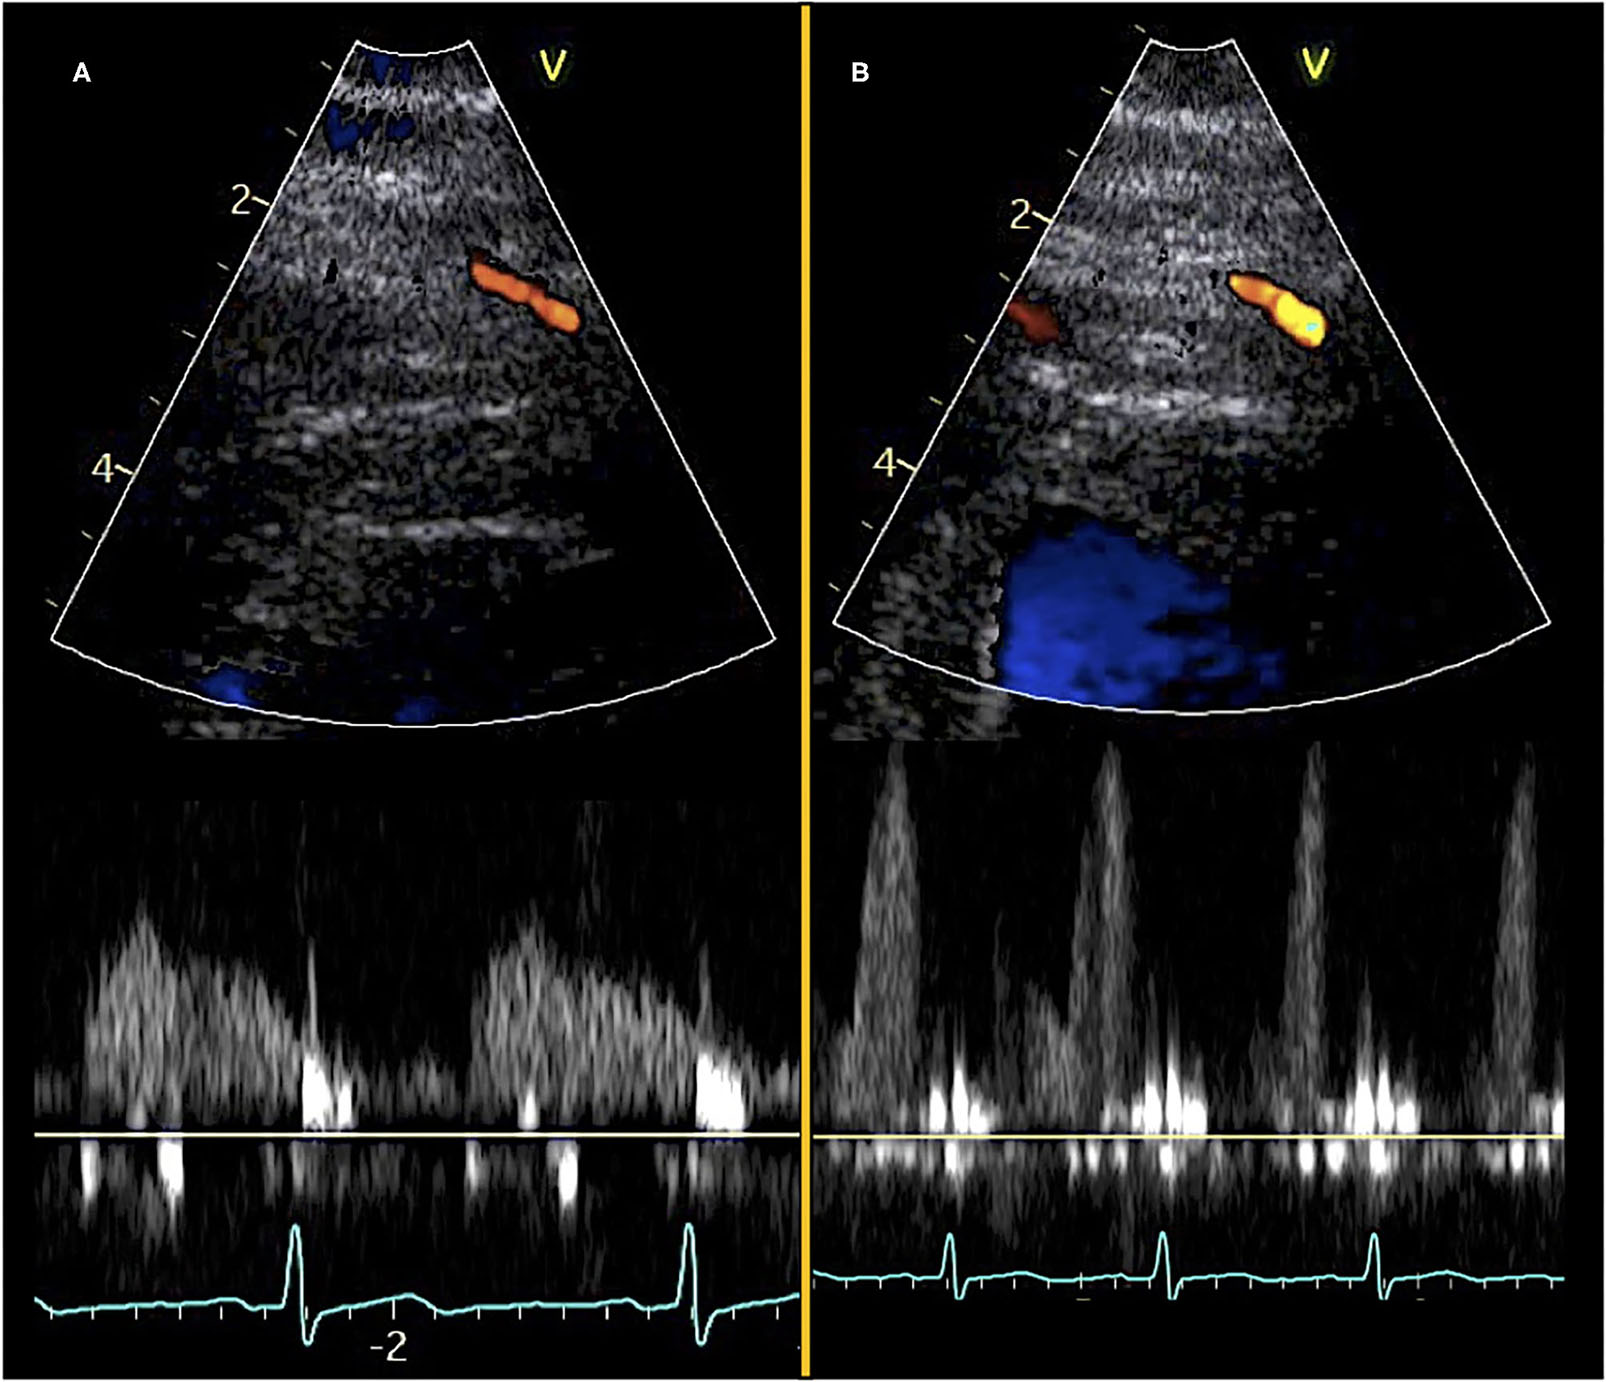

Coronary flow velocity measurements may be obtained in several of the larger coronary arteries. However, in the context of CMD evaluation, the assessment is most commonly performed via identification of the mid-distal LAD due to its position near the chest wall, thus providing reliable and optimal images and flow curves. Nonetheless, if LAD visualization is difficult in selected patients, measurements may also be obtained in other larger coronary branches (8, 16, 25, 30, 32, 33). The TTDE examination may be performed with commercially available ultrasound machines using a phased array high-frequency ultrasound probe usually in the range from >3 to 8 MHz with harmonic imaging to obtain high-resolution color Doppler visualization of the mid-distal LAD (8, 9, 12, 30, 34). The patient is studied in the left lateral decubitus position. A baseline color scale of ~1–2.5 kHz (velocity range of ± 10–24 cm/s) may be used as a standard for obtaining the color Doppler. The mid-distal LAD is usually located in the interventricular sulcus at the midway between a foreshortened two- and three-chamber apical view. However, due to anatomic variations, the use of modified and apical views is often necessary to obtain optimal LAD visualization. Diastolic maximal coronary flow velocities are measured by pulsed-wave Doppler as a flow signal in the LAD toward the transducer (Figure 1, Supplementary Videos 1, 2). The coronary Doppler flow profile is biphasic with diastolic predominance. To avoid systolic motion artifacts and to achieve reproducible maximal velocities the diastolic flow is used for CFVR calculation. The blood flow direction of the LAD is adjusted to be close to parallel with the direction of the pulsed-wave Doppler ultrasound beam and a 3–4 mm sample volume is positioned over the LAD color flow. Sample volume size is adjusted as needed to balance signal intensity and noise. In case of unsatisfactory quality of LAD color signal or flow velocity profile, it is also possible instead to visualize and assess flow in either the right coronary artery (RCA) or posterior descending artery in the posterior interventricular groove (modified two-chamber view) or the circumflex coronary artery (Cx) in the basal part of the lateral left ventricular wall (apical four-chamber view) (33, 35–38). The deeper position of these branches may necessitate the use of an echo probe with a slightly lower frequency range <6 Mhz. Furthermore, if it is not possible to locate the LAD or other coronary arteries due to low image quality or anatomic variation a Doppler echo contrast agent may be infused to increase image quality and Doppler signal, taking care not to misinterpret exaggerated enhancement of the LAD Doppler signal. Current commercially available echo contrast agents used at some centers include sulfur hexafluoride and perflutren, among others (39–43).

Figure 1

Transthoracic Doppler echocardiography and pulsed-wave Doppler curves. Color Doppler visualization of mid-distal LAD (top) and diastolic pulsed-wave flow velocity curves (bottom). (A) Images obtained at rest and (B) images obtained during adenosine stress.